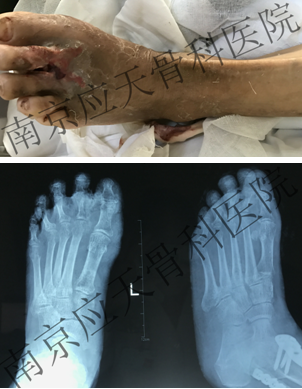

患者江苏丹阳居民,于2019年09月份发现左足底皮肤出现破溃,肿胀,就诊当地卫生院,给予胰岛素控制血糖、输液抗感染对症治疗(具体不详),无好转,左足破溃渗出、肿胀加重,建议上级医院就诊,为进步诊治疗,遂来我院就诊。

患者入院后,完善相关建议检查,明确诊断,排除手术禁忌,行手术治疗。手术顺利完成,术后予以对症治疗,患者伤口愈合。

术前